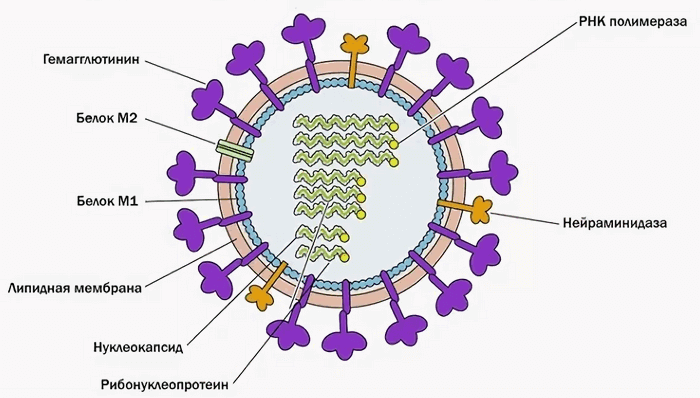

- вирусы гриппа A и B;

Вирусная пневмония характеризуется сезонным характером своего возникновения и регистрируется преимущественно зимой. Вирусы гриппа A (H5N1, H1N1) и B составляют половину возбудителей пневмонии.